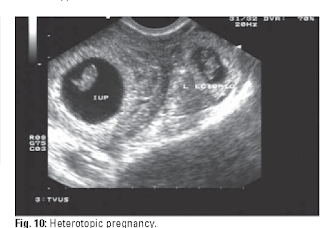

© George CondousSeven apprehensive days later, i.e. three weeks after her first consultation, much to the puzzlement of everyone, a small shadow was seen in the uterine cavity of what appeared like a gestational sac with a yolk sac in-situ. A diagnosis of heterotopic pregnancy (concomitant intrauterine and extrauterine pregnancy) was considered, and laparoscopic evaluation was considered.